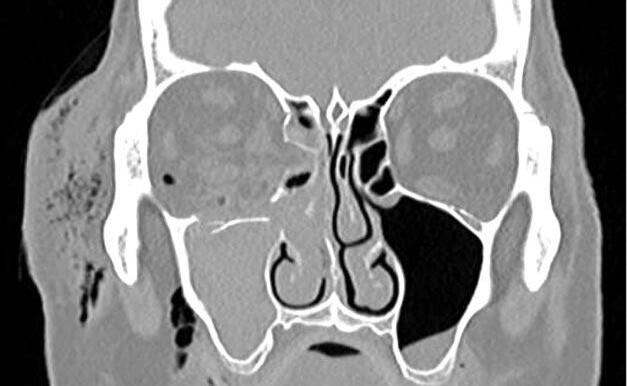

aplicada y despigmentación difusa (signo de “sunset glow fundus”) por la afectación del epitelio pigmentario de la retina (EPR). Teniendo en cuenta los antecedentes clínicos del paciente, se interpretó el cuadro como un VKHlike, Se inició tratamiento con meprednisona oral 20 mg/kg/día e hipotensores oculares tópicos (timolol + dorzolamida). La respuesta antiinflamatoria fue satisfactoria ya que en los controles subsiguientes no se observaban PKs ni células en cámara anterior, sin embargo, la PIO en OD persistió elevada pese al tratamiento hipotensor. En la gonioscopía (figuras 5 y 6) se constató ángulo cerrado con sinequias en los 360º, por lo que se

inició acetazolamida oral 250 mg 3 veces por día y se programó cirugía de implante de válvula de Ahmed en OD, la cual se realizó en marzo 2021.

Figuras 5 y 6: gonioscopía de ambos ojos: ángulo cerrado con sinequias en los 360º.